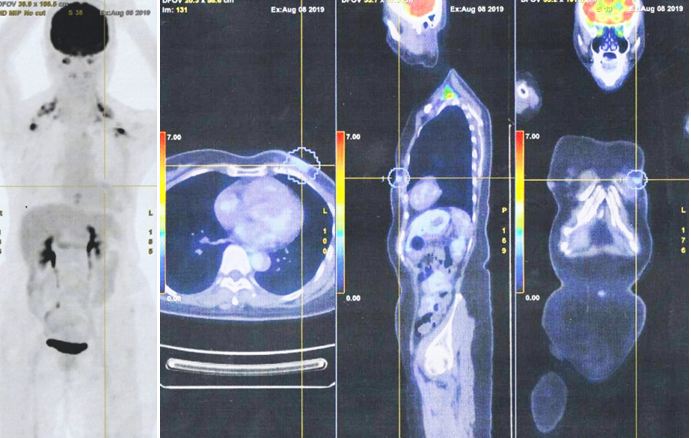

2. Pada tanggal 8 Agustus 2019, saya berkonsultasi dengan dokter spesialis onkologi di sebuah rumah sakit swasta di Kuala Lumpur. Pemindaian PET dilakukan. Hasilnya menunjukkan:

• Serapan FDG derajat rendah terlihat pada perubahan inflamasi pascaoperasi pada dinding dada anterior kiri. Tidak ada nodus hipermetabolik atau metastasis jauh.

18. Hasil tes darah dan PET scan di rumah sakit swasta di Kuala Lumpur adalah:

• PET scan menunjukkan

• Kekambuhan lokal di dada kiri dengan baik,

• Metastasis ke kelenjar getah bening regional dan nodul subkutan, paru-paru, peritoneum dan tulang.

Seperti yang ditunjukkan oleh hasil kasus ini, Lucy telah mengambil jalan yang salah. Dua puluh bulan setelah melakukan apa yang menurutnya benar, kanker Lucy menyebar seperti api liar. Ada metastasis ke kelenjar getah bening regional, nodul subkutan, paru-paru, peritoneum dan tulang (lihat gambar di atas).

Saya mungkin mengatakan saya tidak percaya pada apa yang saya lihat di PET scan – itu benar-benar bencana yang mengerikan. Lucy telah melakukan kesalahan yang tragis.